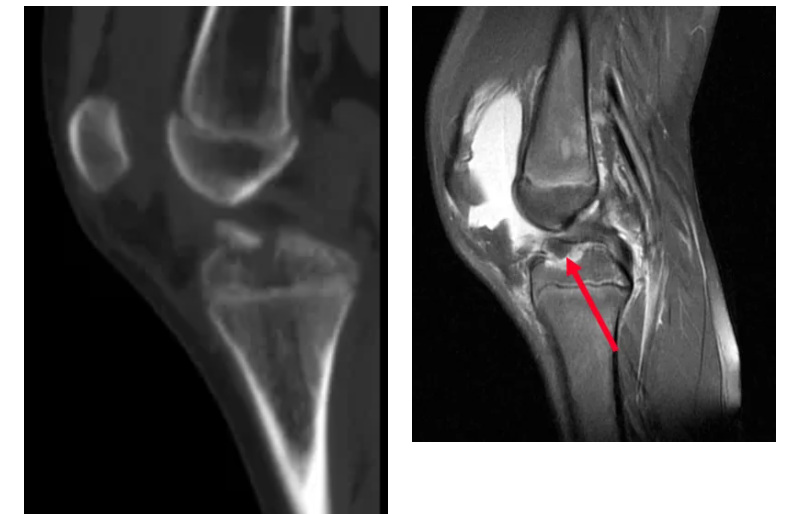

01.交叉韌帶損傷

關(guān)節(jié)鏡下微創(chuàng)韌帶重建

02.交叉韌帶止點(diǎn)骨折(脛骨髁間棘骨折)

關(guān)節(jié)鏡下微創(chuàng)韌帶復(fù)位固定骨折

03.半月板損傷

關(guān)節(jié)鏡下微創(chuàng)行半月板成形、部分切除、盤(pán)狀半月板切除、半月板撕裂縫合等